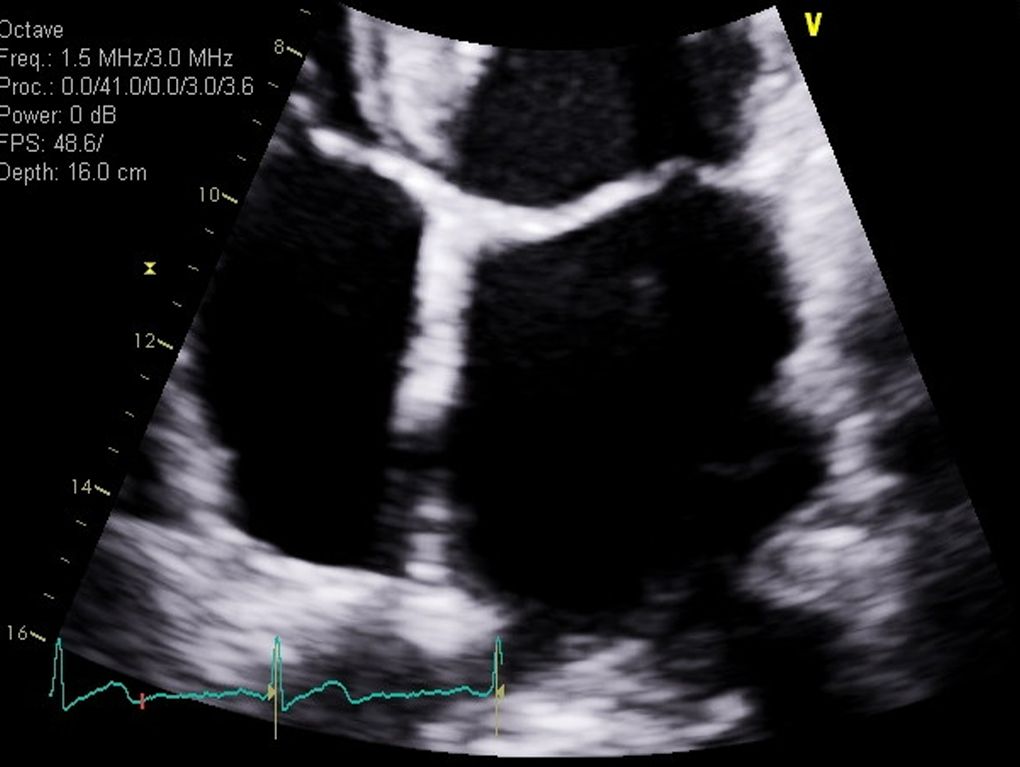

what measurement is this for

RA volume, measure when the chamber is at its largest, just right before the TV open, at end-systole

Trace the chamber excluding the TV annulus

and we also do a length

a normal RA size is going to be less than 19 centimeters squared